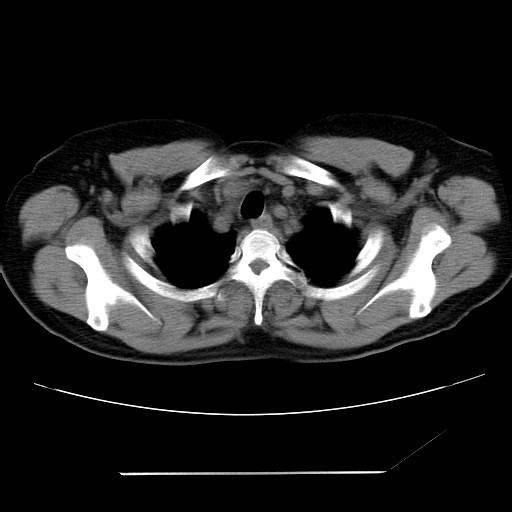

女性,62岁,长期咳嗽,既往从事工作有粉尘接触,有高血压病史,110/150mmhg,近日咳嗽加重,脸面浮肿,请大家帮看下,

1、尘肺;2、慢性支气管炎合并肺部感染;3、心影增大(左房、左室大),考虑高血压性心脏病。